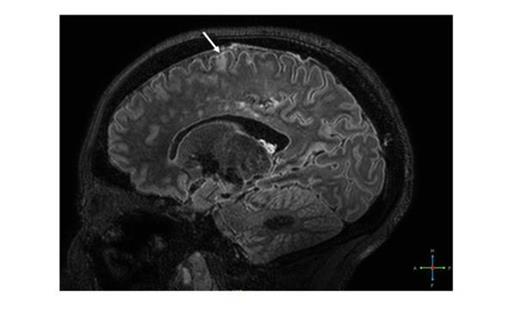

With the exception of two patients, all displayed round and circumscript infarcts in the deep white matter of the frontal or parietal lobe (Table). Most lesions (82%) were <5 mm. In one patient (A) we identified 164 white matter infarcts (Figure 1). Strikingly, one patient (patient B) had several cortical micro-infarcts (Figure 2) although she had no neurological symptoms. These were associated with an occluded A1 and A2 segment of the anterior cerebral artery. In addition, this patient had unique pattern of white matter lesions, consisting of irregular shaped white matter infarcts, some located periventricular, and others close to the cortical infarcts. In two other patients (patients C and D) we identified an isolated cortical micro-infarct despite the absence of large vessel vasculopathy. In patient C, we found numerous hypo-intense areas symmetrically distributed in the deep white matter of the frontal and parietal lobe (Figure 3). These areas were associated with prominent transmedullary veins.

Cortical micro-infarct (arrow) and associated white matter infarcts in patient B, 7T MP-FLAIR image.